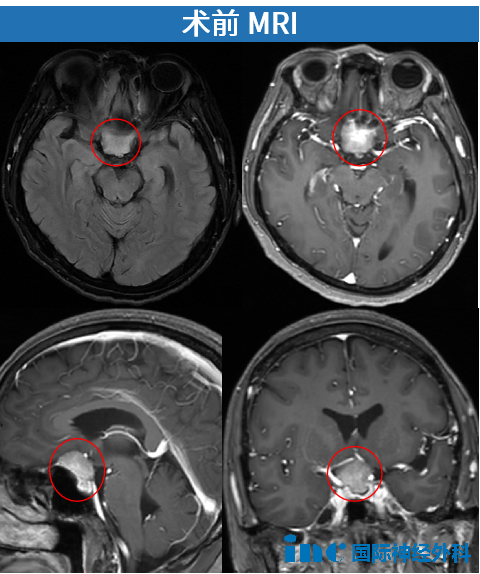

2024年12月17日,遠(yuǎn)在異國(guó)的陳女士因面癱、視物模糊被確診為鞍區(qū)腦膜瘤。病情不等人——短短4天后,她已緊急飛回國(guó)內(nèi)。進(jìn)一步檢查顯示,腫瘤匍匐于鞍底,約2.6cm×2.5cm。

鞍區(qū)腦膜瘤影像

時(shí)間一天天流逝,光明也一點(diǎn)一點(diǎn)被吞噬。兒子一邊安撫著害怕的母親,一邊全力奔走。2025年1月3日,他們終于拿到巴教授的關(guān)鍵評(píng)估:“手術(shù)非常緊急!”因?yàn)榇藭r(shí)陳女士雙眼視力正在持續(xù)下降,檢查顯示雙眼視力0.2(正常1.0),雙眼視野嚴(yán)重缺損。

由于這個(gè)腫瘤位于前顱底,從兩條視神經(jīng)之間生長(zhǎng),并隨著其增大逐漸壓迫了視神經(jīng)。此外,腫瘤的位置十分險(xiǎn)要,還波及到了垂體及垂體柄。

這不僅僅是腫瘤的問(wèn)題,腫瘤還會(huì)壓迫供應(yīng)視神經(jīng)和視交叉的血管,損傷視神經(jīng)的血液供應(yīng),這很容易導(dǎo)致腫瘤和視神經(jīng)的梗塞,患者可能會(huì)完全失明。